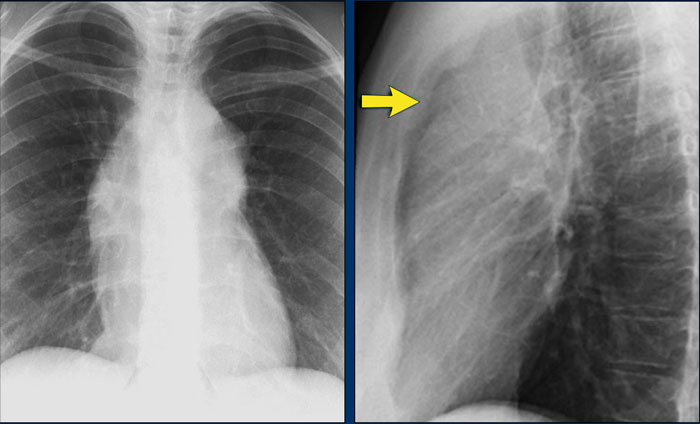

Case Example: Subtle Signs of Congestive Heart Failure

Begin by reviewing these current chest radiographs.

Based solely on these images, one might suspect congestive heart failure (CHF), though the findings are subtle.

Now review the previous study…

Scrolling between the current and prior films significantly increases diagnostic confidence in your diagnosis of congestive heart failure.

Key comparative findings include:

• Cardiac size: Slightly increased compared to the previous study; however, cardiomegaly was already present.

• Pulmonary vasculature: Mild vascular engorgement suggesting elevated pulmonary venous pressure.

• Interstitial markings: Subtle signs of interstitial edema .

• Pleural effusions: Bilateral small effusions, with subtle changes in the inferoposterior borders of the lower lobes, suggesting fluid accumulation.